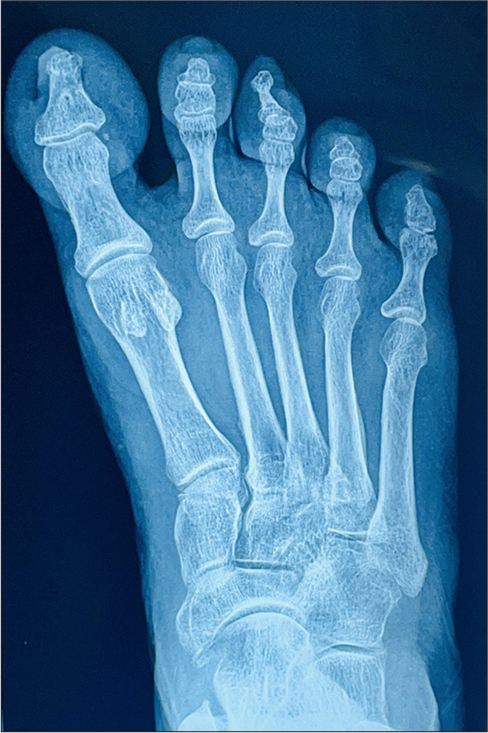

A 47-year-old woman presented with an asymptomatic thickened growth projecting beneath the nail plate of the left middle toe for the past 3 years. The lesion initially started as a small, thickened nodule beneath the nail plate, which gradually progressed in size. She had no other complaints and no similar symptoms in her family members. Cutaneous examination revealed a well-defined, hard, fixed, non-tender nodule with an irregular hyperkeratotic surface on the tip of the left middle toe [Figure 1]. Based on the clinical findings, we thought of verruca vulgaris, subungual exostosis, fibroma, acquired digital fibrokeratoma, osteochondroma, enchondroma, or nail bed tumour as differential diagnoses. Radiographic imaging of an anteroposterior view of the left foot revealed a small exophytic bony lesion arising from the tuft of the middle toe, showing no obvious continuity with the medulla of the phalanx. This was suggestive of a subungual exostosis. Besides, there was sclerosis of the phalangeal shaft. No associated cortical irregularity, periosteal reaction or soft-tissue component was seen [Figure 2]. Based on these findings, a diagnosis of subungual exostosis was made. The patient was referred to an orthopaedic surgeon for excision of the lesion.

- A small bony protuberance arising from the phalangeal tuft of mid toe.

- An anteroposterior view of the left foot shows a small exophytic bony lesion is seen arising from the tuft of middle toe showing no obvious continuity with medulla of phalanx- subungual exostosis. There is sclerosis of this phalangeal shaft. No associated cortical irregularity, periosteal reaction or soft tissue component is seen.